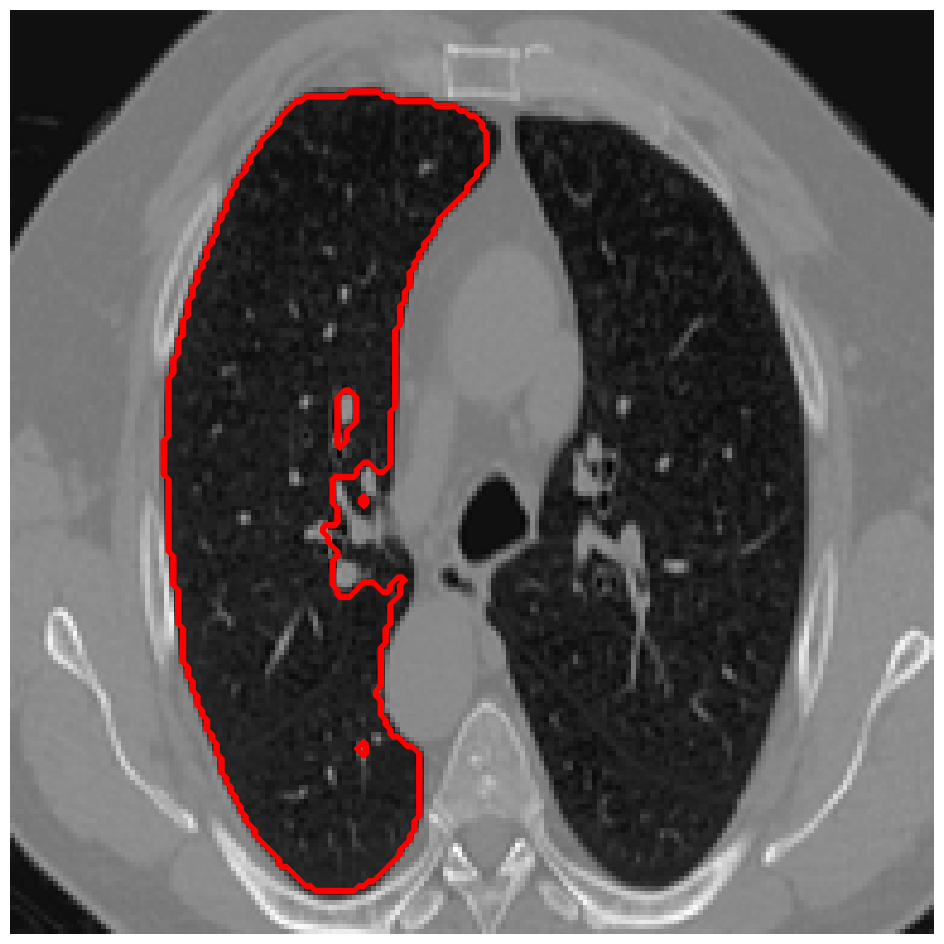

Figure 3: A sample result on the Lung data. We display the input image with the user input \mathcal{M}, the ground truth (GT) and results from the four methods. Moreover, we show comparisons with the model (4) solved in a variational framework with both Total Variation (TV) and Euler Elastica as explicit regularisation, as well as a comparison with the model solved in a Deep Image Prior framework.

In Figures 3 and 4 we show two select images from the test set for the Lung images to qualitatively show some results. To begin, we show some results of the model (1) solved with a Total Variation (TV) [21] regulariser, and with a Euler Elastica [22] regulariser. In addition, we show a result with the model (1) in a typical Deep Image Prior framework (i.e. training a network specifically for that image without the explicit regularisation in the loss function, employing early stopping). We see that the result from M4 is an improvement over the TV and Elastica models, whereas results from the DIP example is comparable. However, the DIP example requires a new network trained specifically for the new image, whereas our result is acquired after training. In addition to the explicit regularisation comparison, we also display the results from the four methods (all of which are trained previously on 222 images and used for prediction). Moreover some quantitative results are shown in table 1, which shows the mean DICE score and standard deviation on the 16 images in the test set.